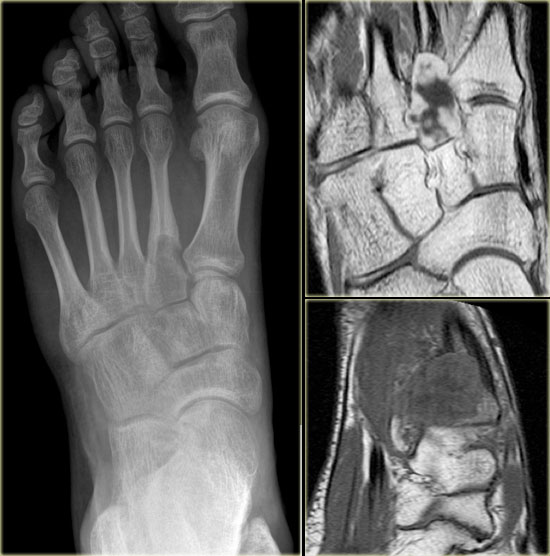

Chondromyxoid fibroma (3)

On the left a well-defined lytic lesion at the base of the 2nd metatarsal bone.

There is no mineralisation.

T1-weighted images before and after Gd-DTPA demonstrate some expansion and lobulation.

On the T1-weighted image before contrast there is a nonspecific intermediate signal intensity.

After the administration of Gadolinium there is thick peripheral enhancement.

Differential diagnosis based on plain radiograph: giant cell tumor or chondroid lesion, i.e. enchondroma, low grade chondrosarcoma or CMF.

Biopsy revealed CMF.

Although this is a rare lesion, the foot is one of the preferential sites of origin.